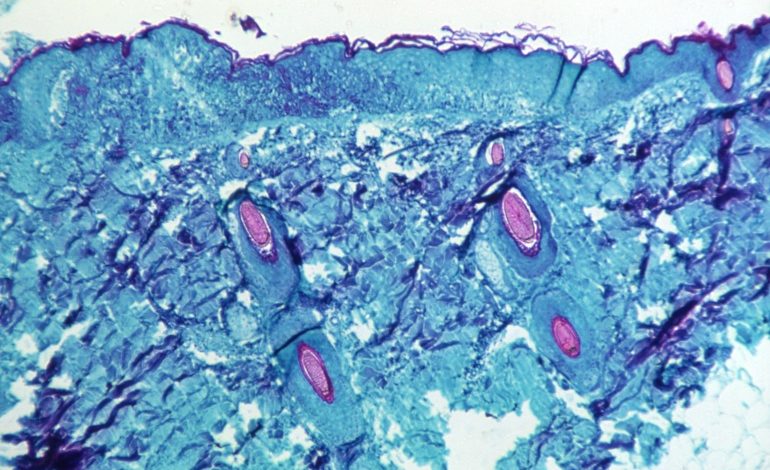

وتظهر أعراض المرض على هيئة حمى وتضخم الغدد الليمفاوية وآلام في العضلات والتهاب حلق، إضافة إلى الإرهاق والقشعريرة وطفح جلدي يشبه جدري الماء على اليدين والوجه وباطن القدمين والأعضاء التناسلية وغيرها من أجزاء الجسم.

واكتشف جدري القرود أول مرة عام 1958 عندما ظهر مرض يشبه الجدري في قرود أحد المختبرات، ومن هنا أُخذت هذه التسمية.